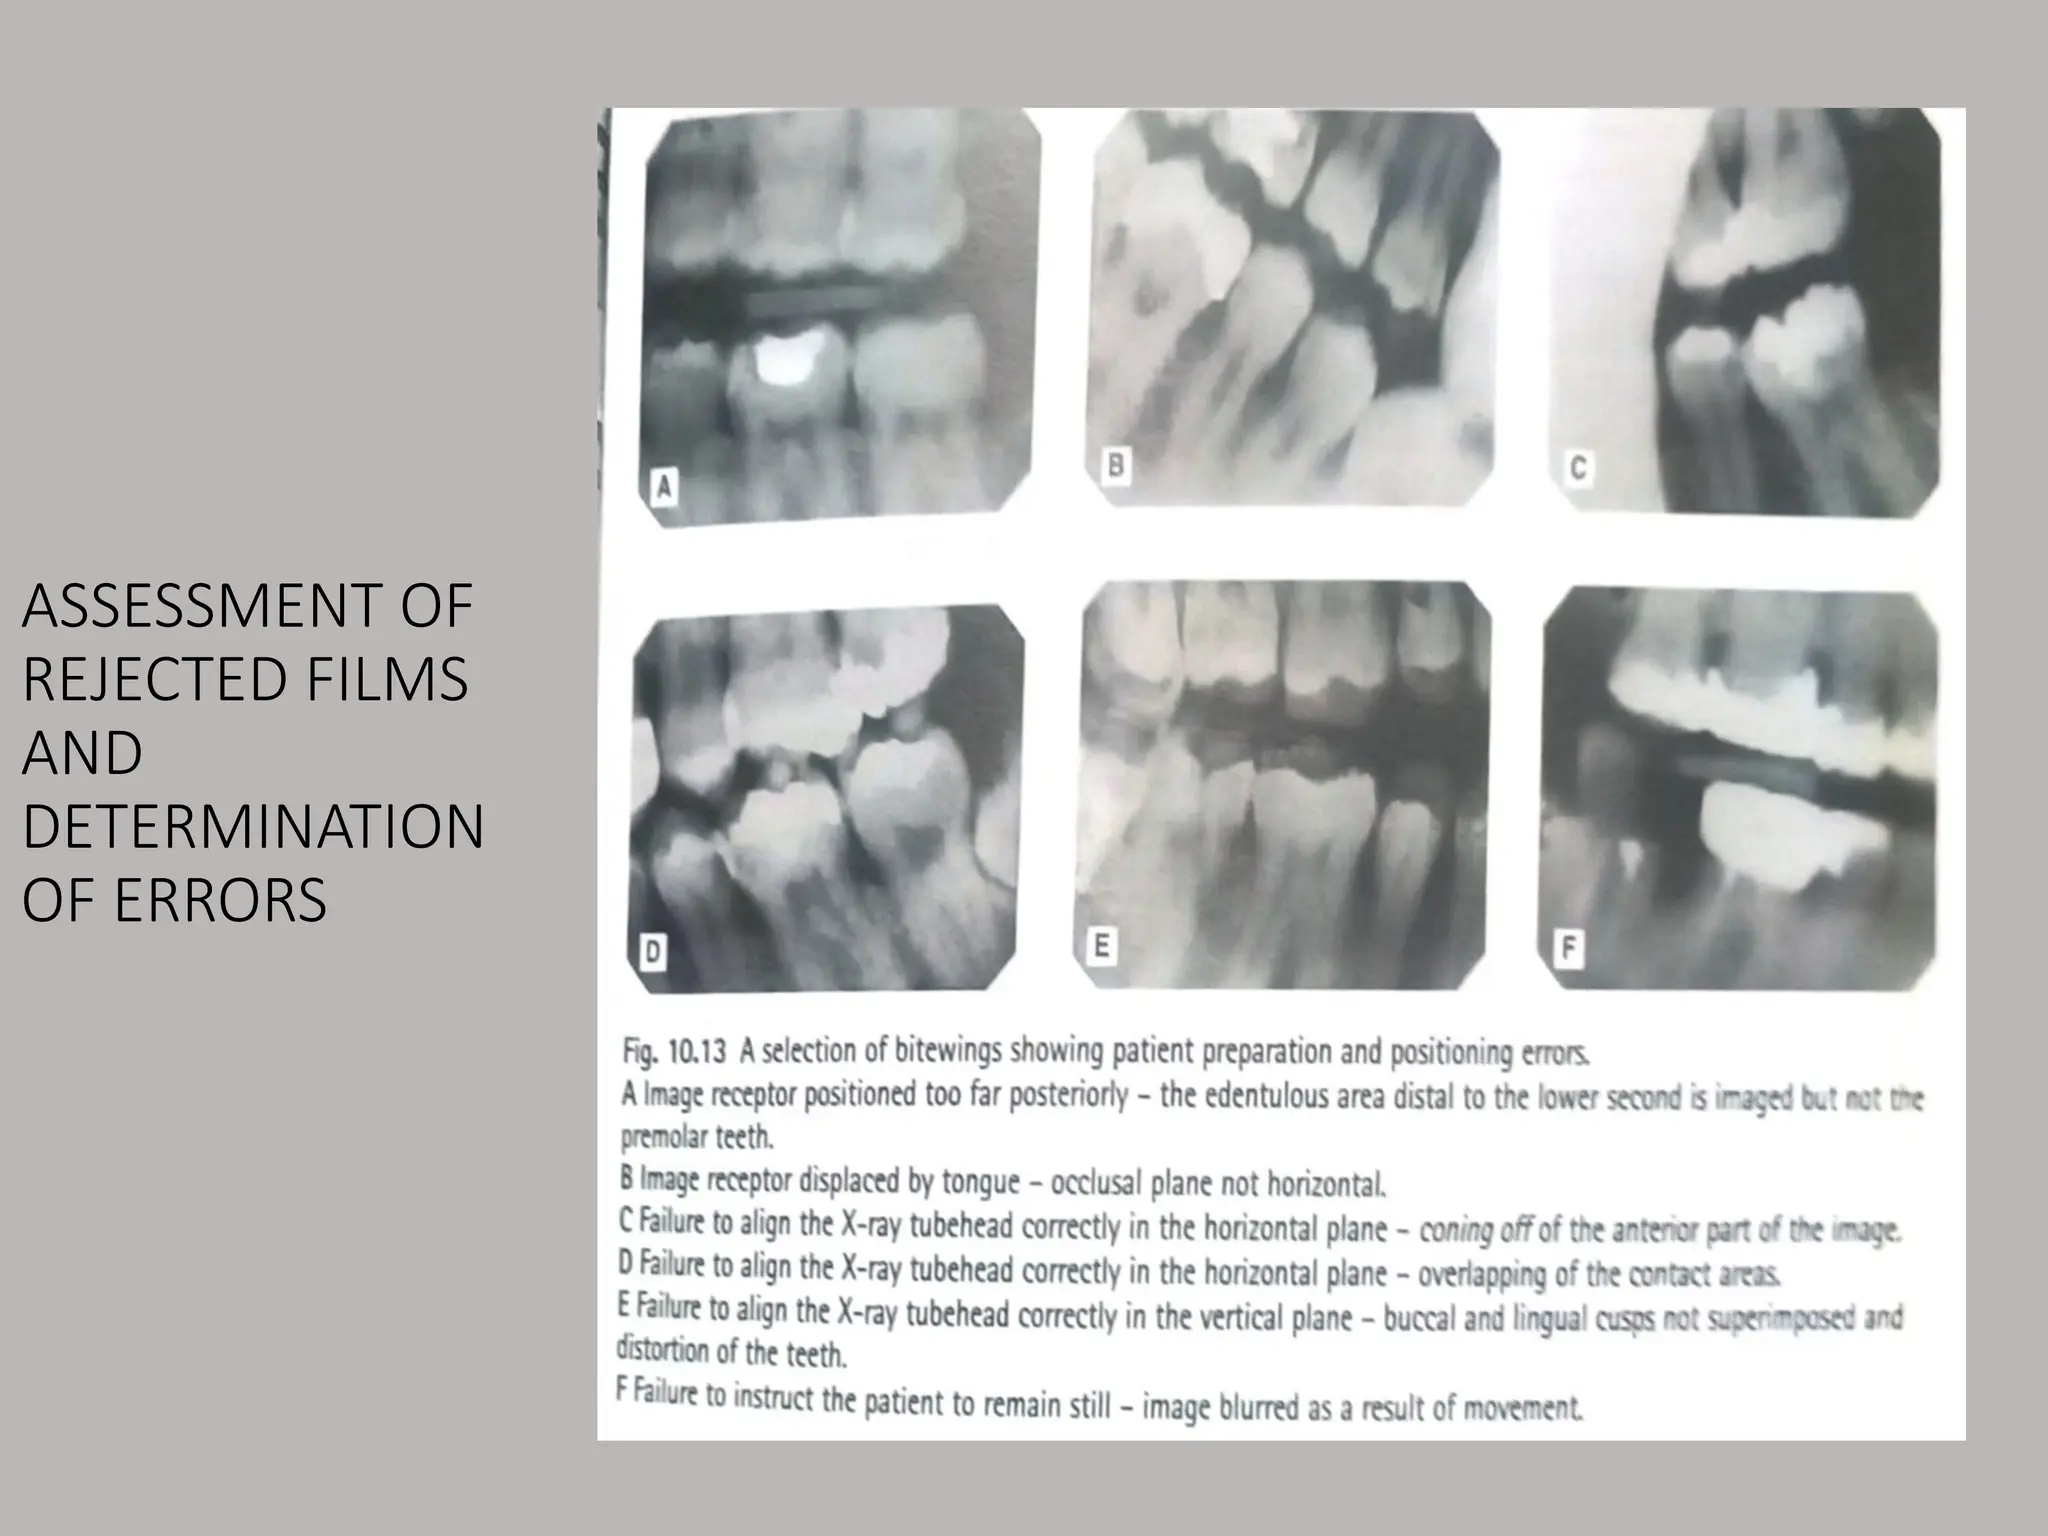

ASSESSMENT OF

REJECTED FILMS

AND

DETERMINATION

OF ERRORS